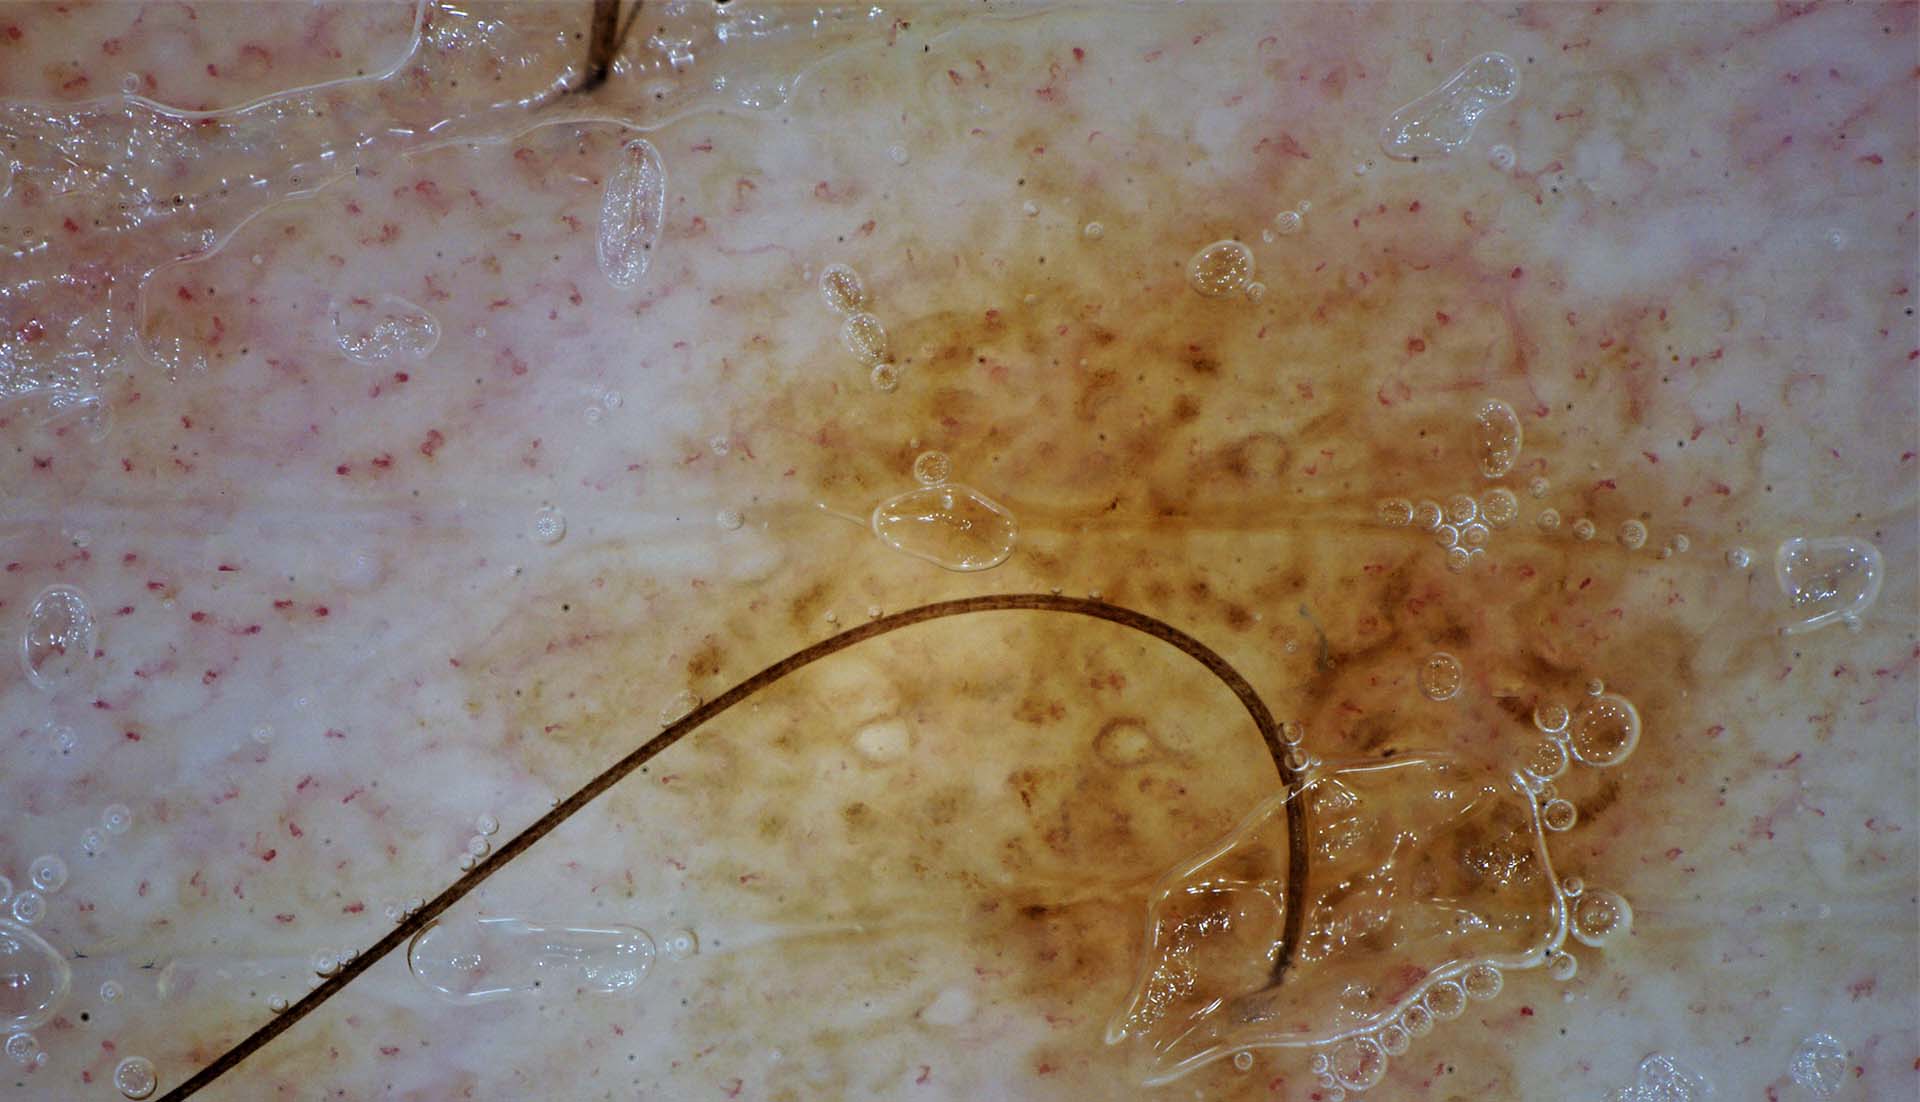

Razor

Spesso le immagini dermoscopiche delle lesioni cutanee appaiono parzialmente coperte dai peli,il che rende la valutazione delle caratteristiche del neo più complicata per il clinico.

Una possibile soluzione è quella di tagliare o sradicare eventuali capelli presenti sulla lesione cutanea, ma questo non è sempre auspicabile.

Il software IRSkin offre una soluzione diversa, la funzione Razor, che tenta un’eliminazione algoritmica dei peli.

Prima di usare razor

Dopo aver usato razor